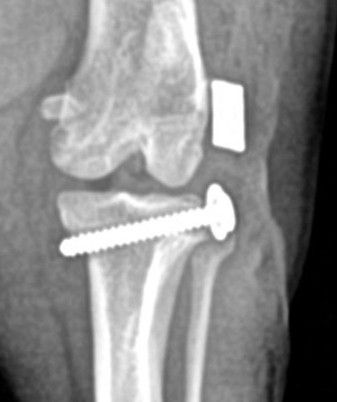

Tibial plateau leveling osteotomy surgery involves changing the anatomy of the knee